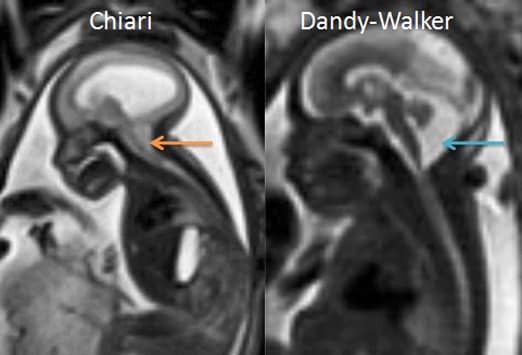

МРТ снимки мальформации Денди-Уокера